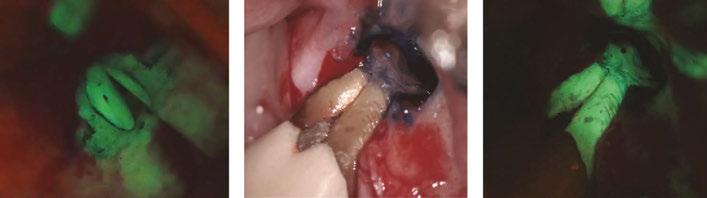

Figure 4A-4C: 4A. Maxillary lateral incisor with an internal resorption at the coronal third. 4B. Mandibular canine with an internal resorption in the middle-apical area. 4C. Mandibular molar with an irregular internal resorption in the coronal portion Figures 5A-5C:

When the IRR communicates with the periodontium area, MTA, Biodentine® (Septodont USA) or similar product is the filling of choice,3,4 (Figures 5A, 5B, 5C).

5A. Preoperative X-ray. 5B. Immediate postoperative X-ray. 5C. Follow-up after 1 year and 9 months EP